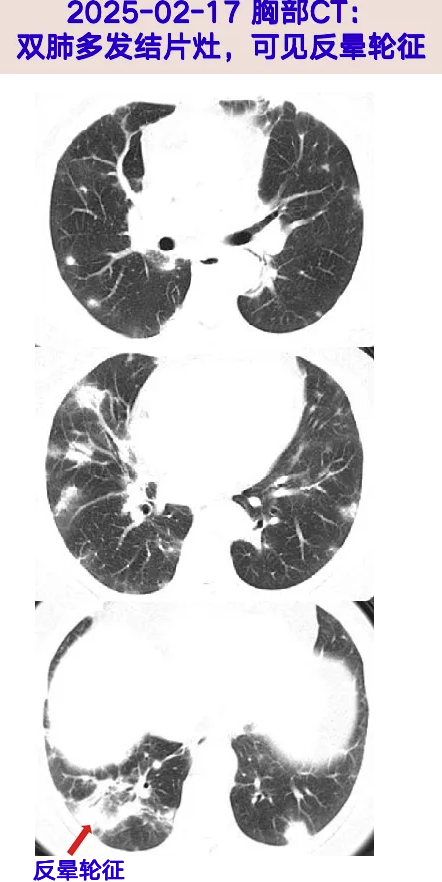

胸部增强CT:两肺胸膜下区为主散在多发斑片、结节状密度增高影伴实变,可见支气管充气征,右下肺病灶见反晕轮征。

病史特点:中老年女性,临床表现为急性发热伴气促,经验性抗感染治疗(拉氧头孢、阿莫西林等)效果不佳,实验室检查见炎症指标CRP轻度升高,部分肿瘤标志物升高,胸部CT表现为两肺散发斑片、结节状密度增高影伴实变,可见反晕轮征,需考虑以下鉴别诊断:

2、真菌性肺炎:本例患者急性呼吸道症状起病,CT见两肺多发结片影,右下肺病灶见反晕轮征,常规抗细菌治疗效果不佳,虽GM试验阴性,仍需警惕肺内真菌感染(如曲霉菌、毛霉菌)的可能,可进一步完善痰真菌涂片+培养,真菌三联检(曲霉菌属、新型隐球菌、耶氏肺孢子菌),必要时可行CT引导下肺穿刺活检、支气管镜检查,通过BALF及肺组织的病原学涂片培养、mNGS及病理结果明确诊断。

4、机化性肺炎:患者症状主要表现为发热、气促,血白细胞不高,CRP稍高,同时生素治疗效果不佳,影像学见两肺散发结节、斑片影伴实变,部分可见“反晕轮征”,故机化性肺炎诊断不除外,考虑机化性肺炎为排他性诊断,入院后需进一步完善行经皮肺穿刺或经支气管镜肺活检明确病理。

中老年女性,急性发热伴气促起病,CRP轻度升高,胸部CT见两肺散发结节、斑片状影伴实变,可见“反晕征”,抗菌药物治疗无效;CT引导及支气管镜下肺组织活检,病理见胶原纤维组织略增生、间质内少量急慢性炎症细胞浸润,免疫组化、特殊染色均无殊,病原学涂片、培养、CT引导下肺穿刺组织mNGS均阴性,仅TBLB肺组织mNGS检出少许铜绿假单胞菌(定植不除外);后续患者经糖皮质激素治疗后症状好转、炎症标志物正常,肺内病灶明显吸收,故考虑机化性肺炎诊断明确。

机化性肺炎(organising pneumonia,OP)被认为是一种肺组织损伤后的修复模式,组织学上表现为远端气腔(肺泡腔、肺泡管及细支气管)内存在的息肉样栓子,主要由成纤维细胞、肌成纤维细胞和疏松结缔组织基质构成。其发病机制尚不明确,根据病因分为无明确诱因的隐源性机化性肺炎(COP)和继发于感染、结缔组织病、肿瘤等的继发性机化性肺炎(SOP)。OP的临床症状无特异性,可有咳嗽咳痰、发热、乏力等,影像学典型表现为肺外周或支气管血管周围的斑片状阴影,呈游走性,还可表现为伴有支气管充气征的肺实变、磨玻璃影、反晕征及网状结构等。该例患者肺部病灶表现为两肺散发的结节、斑片状影伴实变,尤其是有下肺慢性炎症灶见“反晕征”,与OP相符。